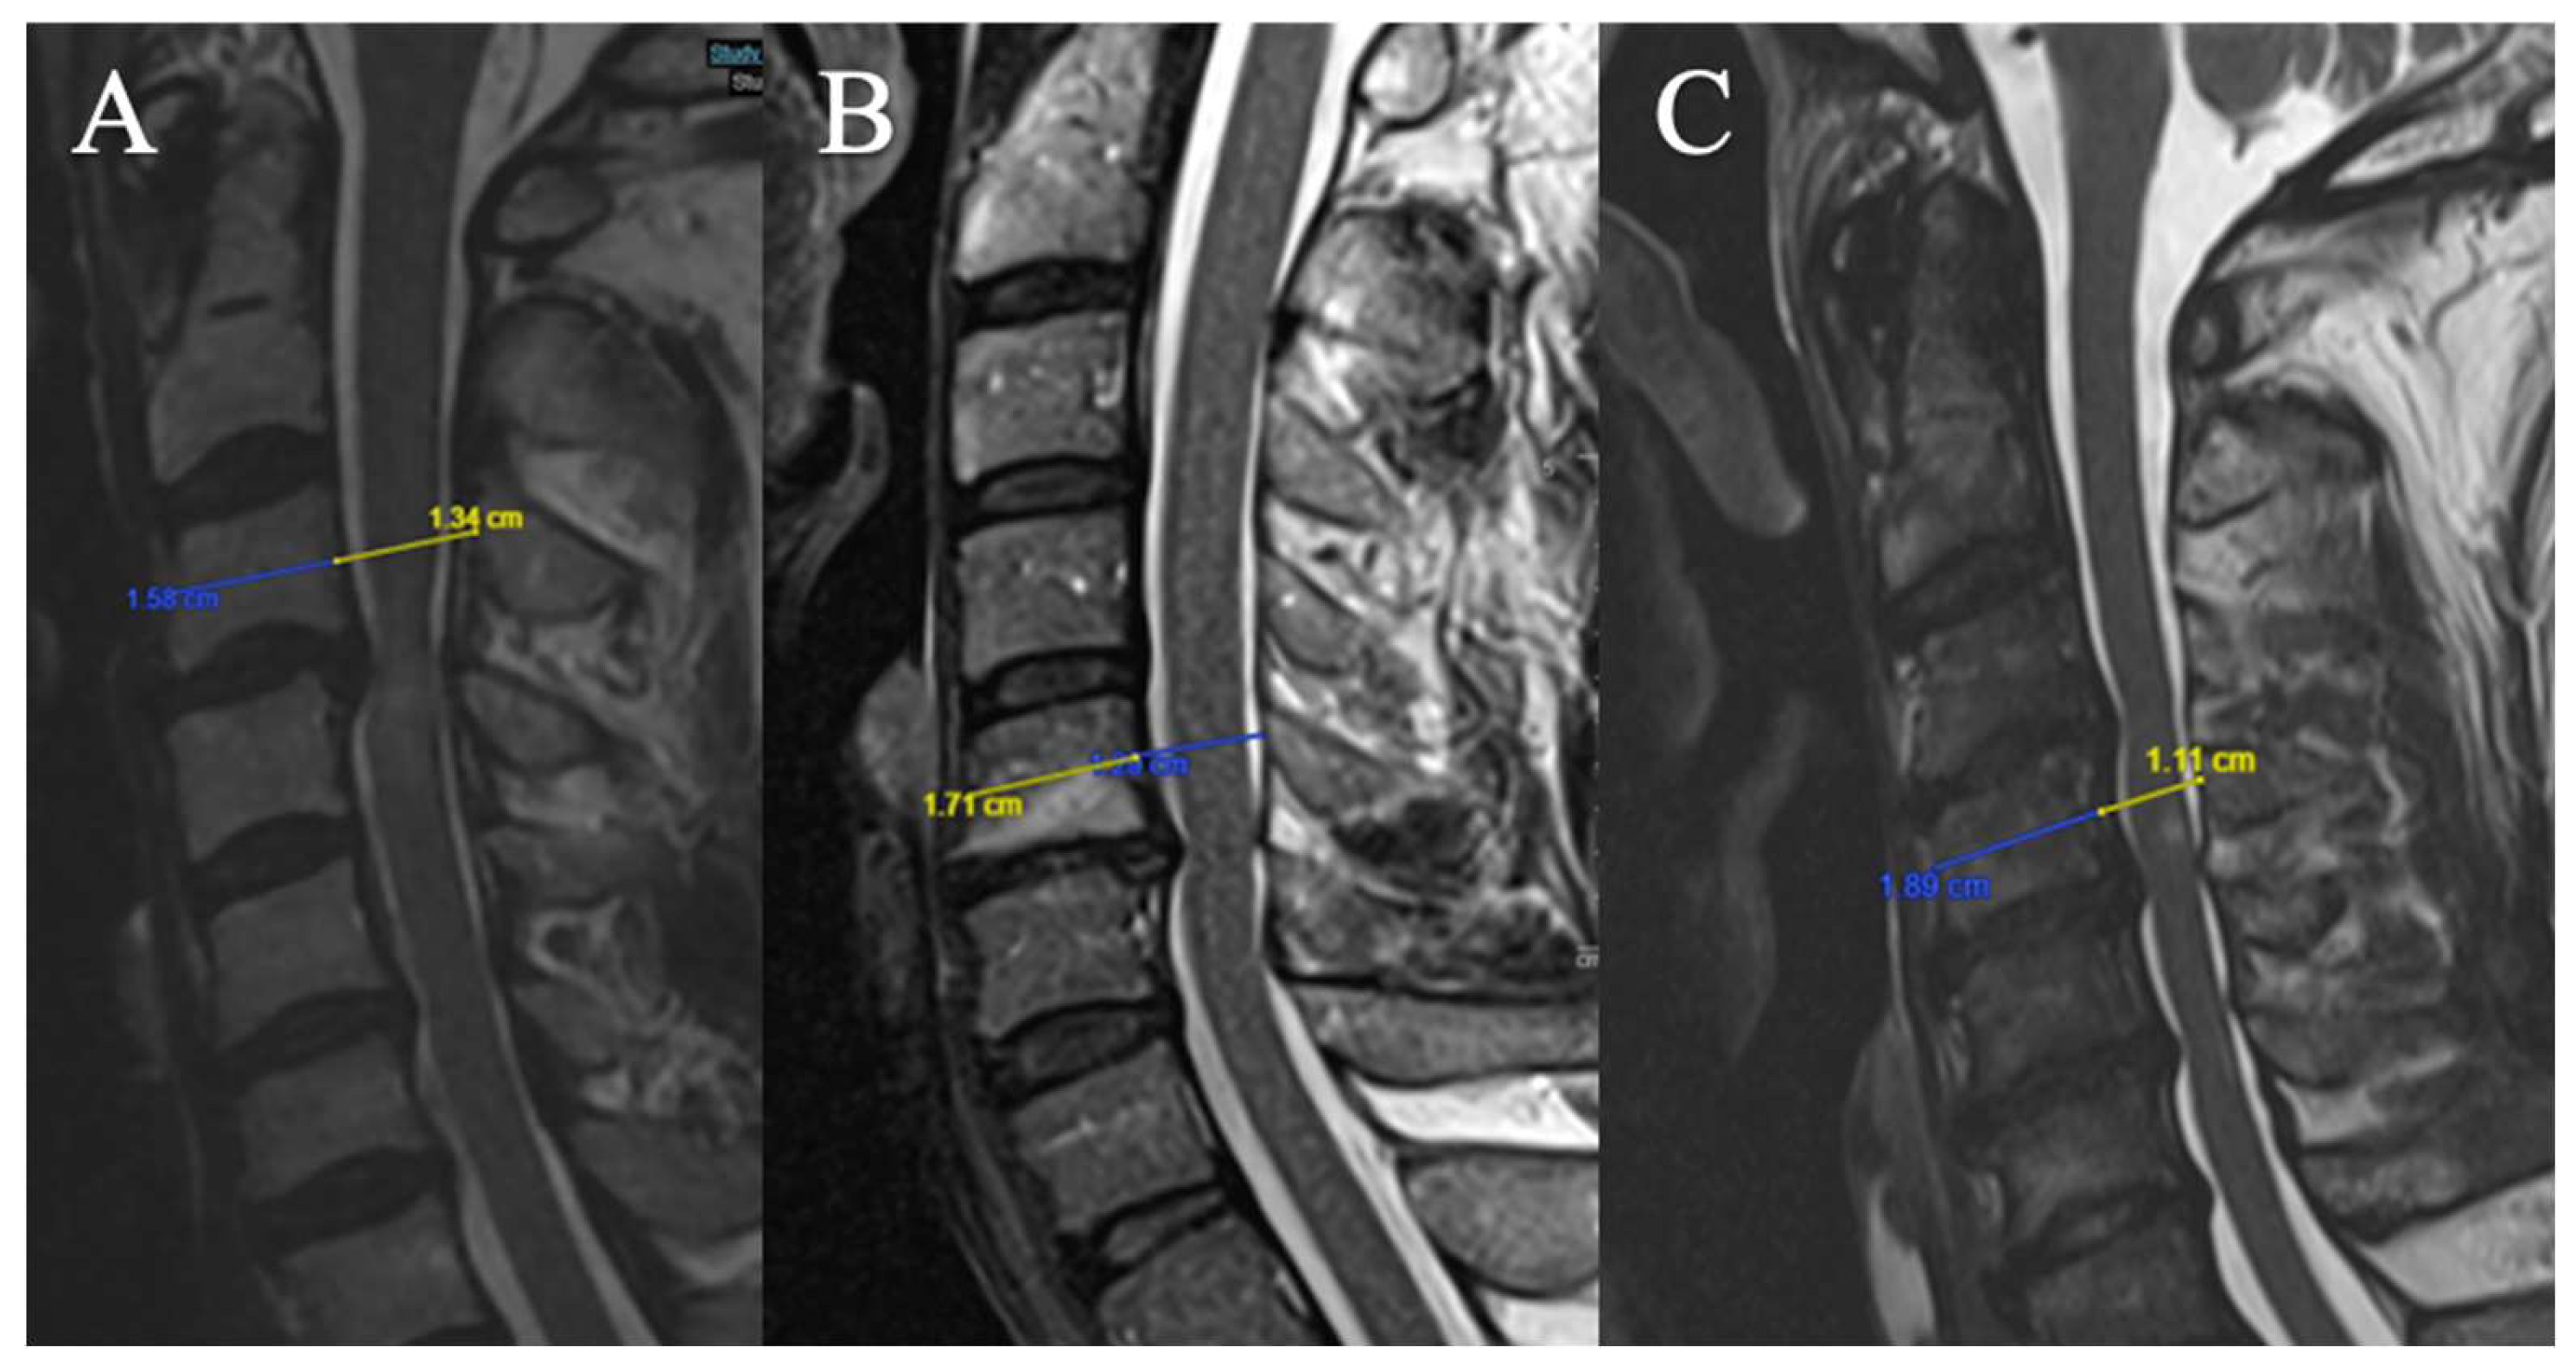

Torg-Pavlov Ratio

3 grades have been selected (based on T2-weighted sequence on the median sagittal sections at the middle vertebral level overlying the compression) (Figure 4):

(A) TPR ≥ 0.8

(B) 0.6 ≤ TPR < 0.8

(C) TPR < 0.6

Local Kyphosis

2 grades have been selected (Focal angle measured on sagittal T2-weighted MRI sequences at the level of maximum compression) (Figure 5):

(A) Lordosis or LK <4°

(B) LK ≥ 4°

Figure 4. Example of measurement of the TPR. (A) TPR = 0.85 ; (B) TPR = 0.75; (C) TPR = 0.59.

Figure 5. Example of measurement of the local angle. (A) LK = 2.2°; (B) LK = 6.A°.